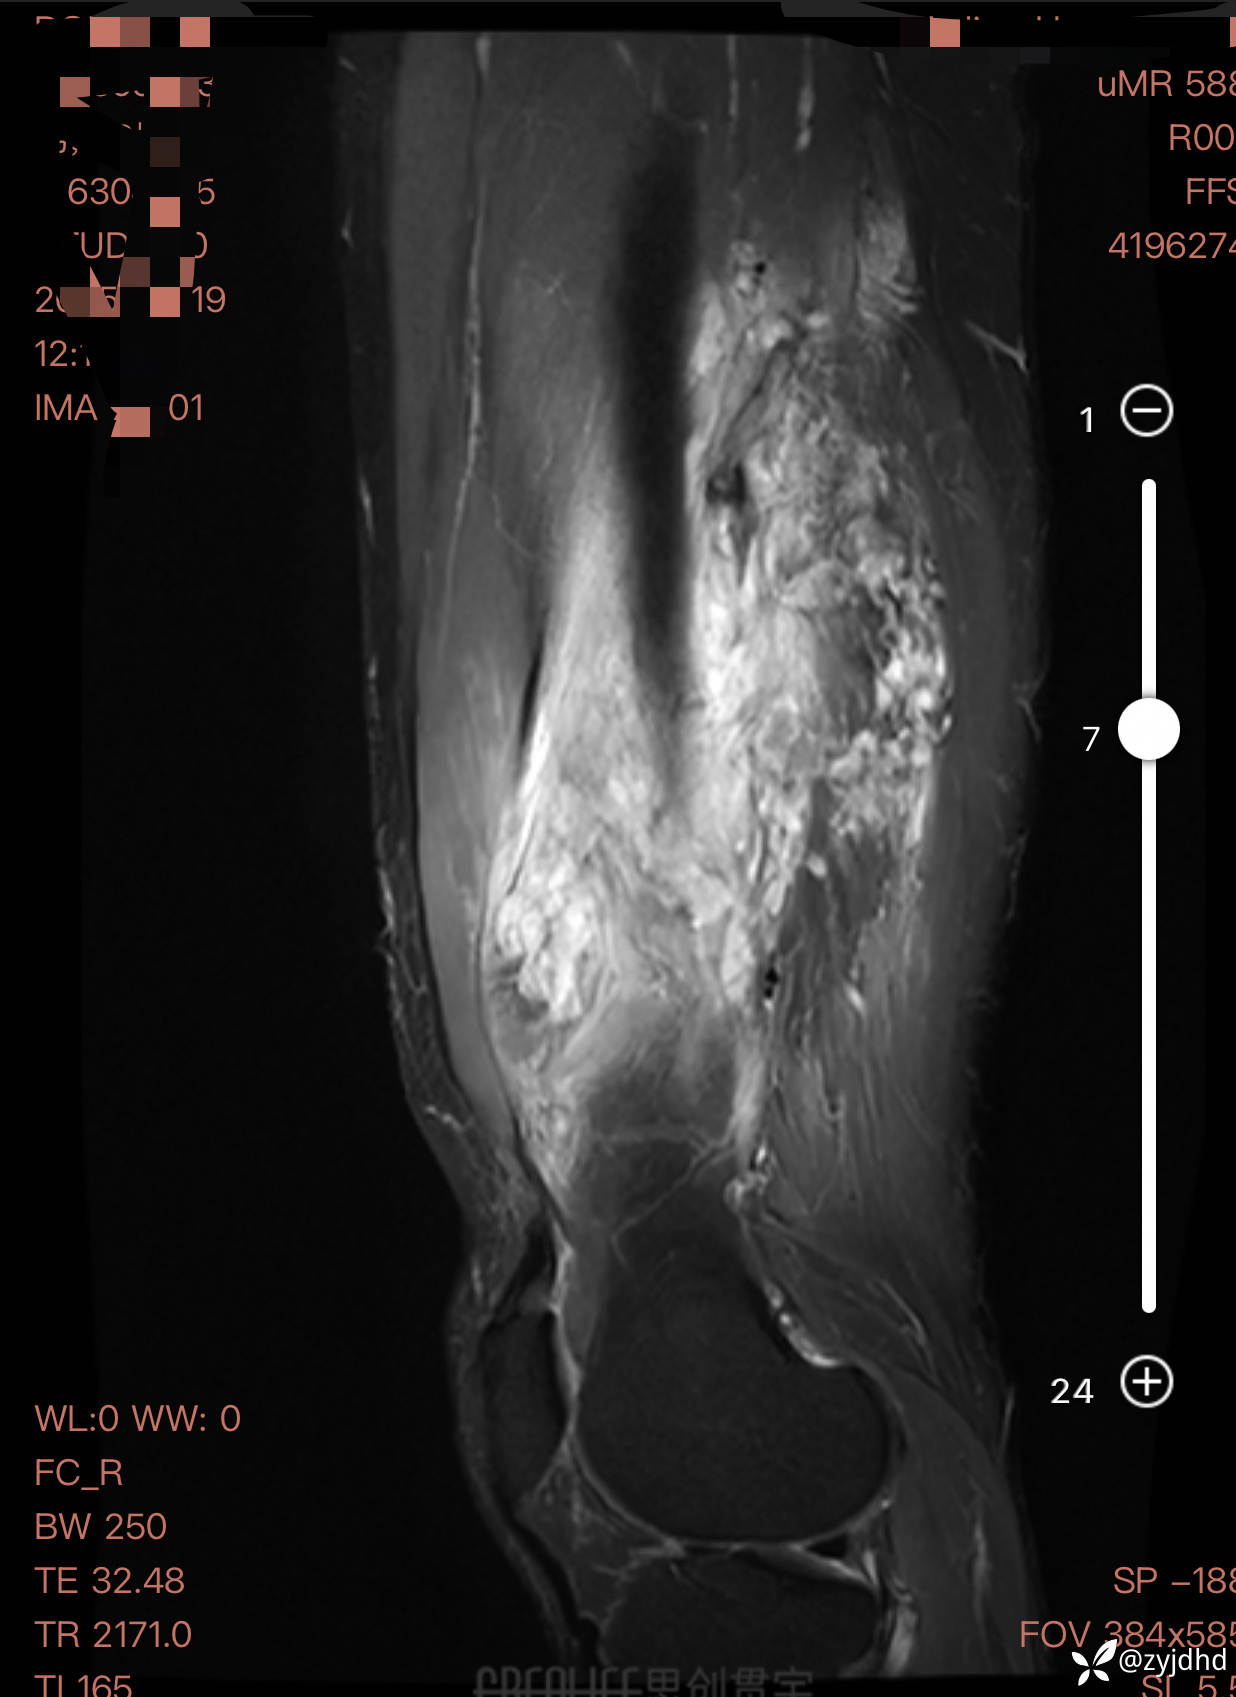

男性,发现右大腿肿物20年。

考虑什么诊断?治疗方案